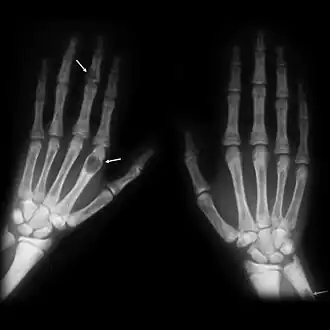

| Brown tumours of the hands in a patient with hyperparathyroidism. | |

The brown tumor is a bone lesion that arises in settings of excess osteoclast activity, such as hyperparathyroidism. They are a form of osteitis fibrosa cystica. It is not a neoplasm, but rather simply a mass. It most commonly affects the maxilla and mandible, though any bone may be affected.[1] Brown tumours are radiolucent on x-ray.

Radiographically, brown tumor may show no detectable changes or a generalized osteoporosis. Partial loss of lamina dura around the teeth may occur but is not a constant feature. Focal Lesions (Brown Tumor) present as sharply defined, round or oval radiolucent areas which may appear multilocular. Such lesions occur more frequently in mandible than maxilla [7]